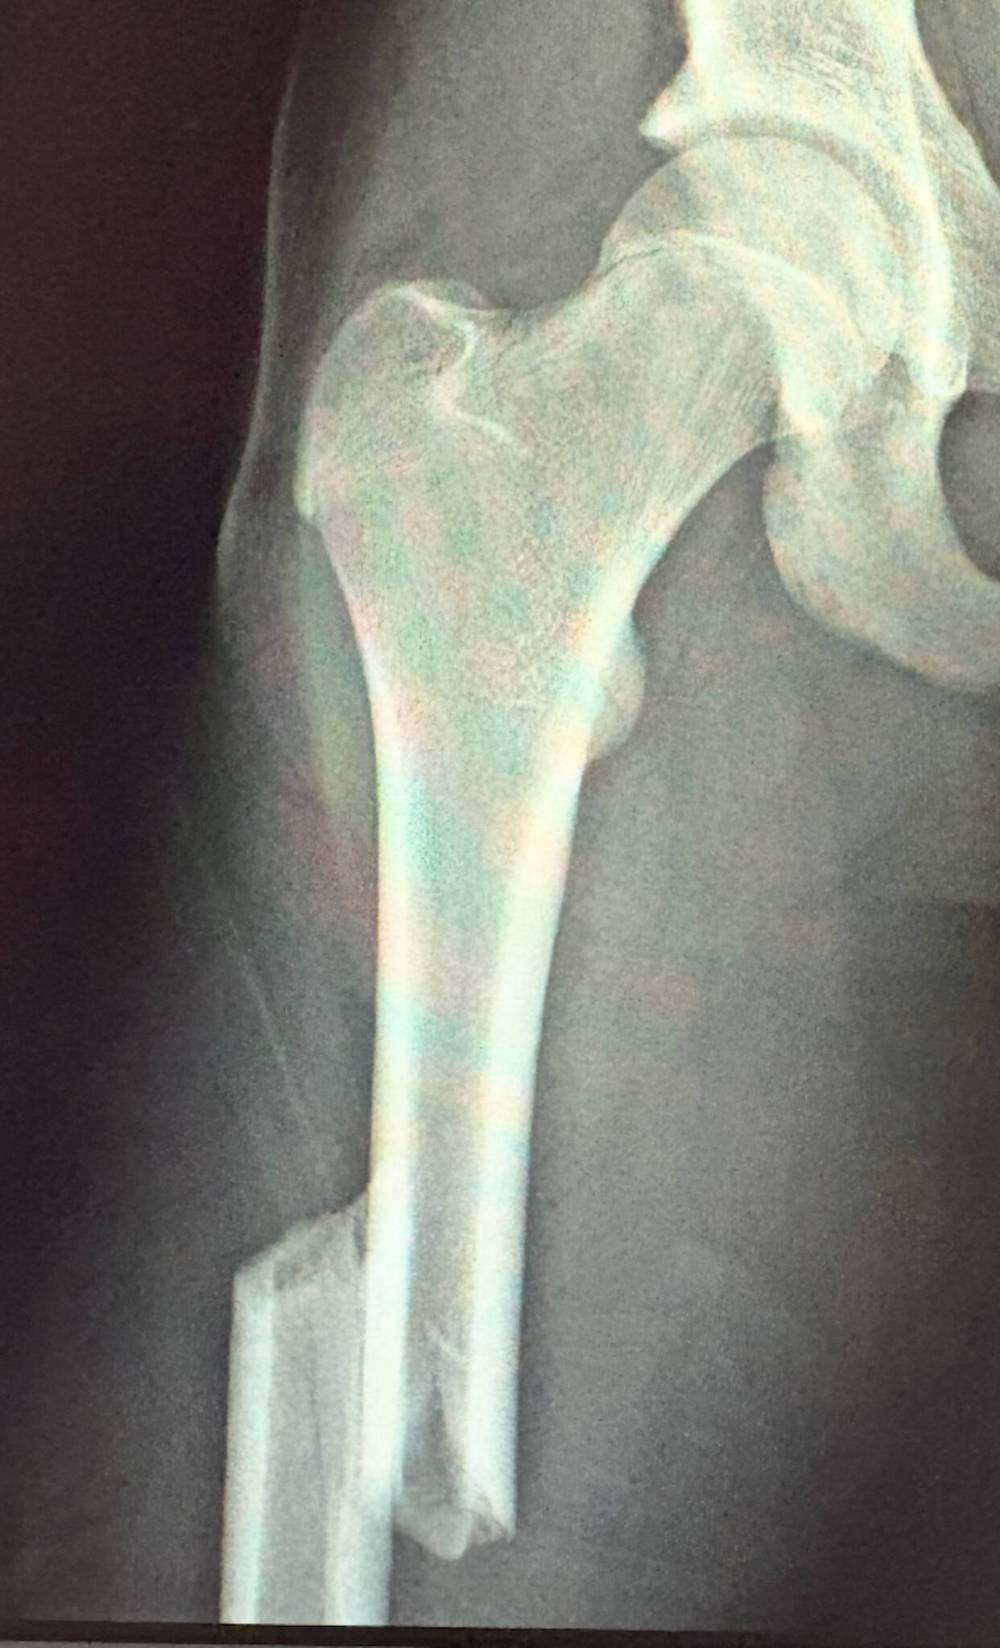

An X-ray of Talon Scinocca's broken right femur shows the damage after he took a hit from behind on Dec. 6, 2025. (Submitted)

The injury didn’t take long to diagnose: X-rays clearly showed Scinocca had broken the femur on his right leg.

“They said it was kind of best case that it snapped so cleanly because it was easier to fix,” father Dave said. While some teenagers might not be interested in receiving a lot of assistance from their mom, Talon was grateful she was there.